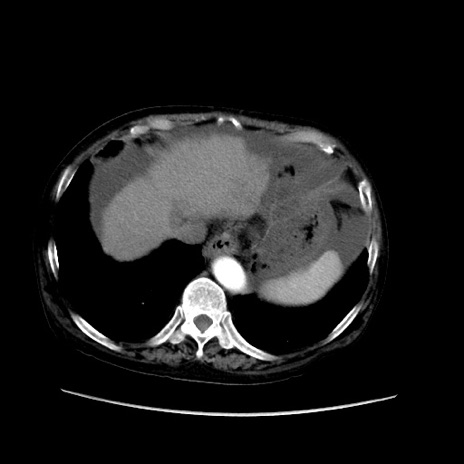

症例31(横断像)

【症例】80歳代 女性

【主訴】腹部膨満感

【現病歴】他院にて肝硬変にてフォロー中。1週間前から便秘、腹部膨満感、臍部腫瘤あり受診となる。

【既往歴】肝硬変

【身体所見】腹部膨隆あり、皮膚変化なし、疼痛なし。

【データ】WBC 4600、CRP 0.25